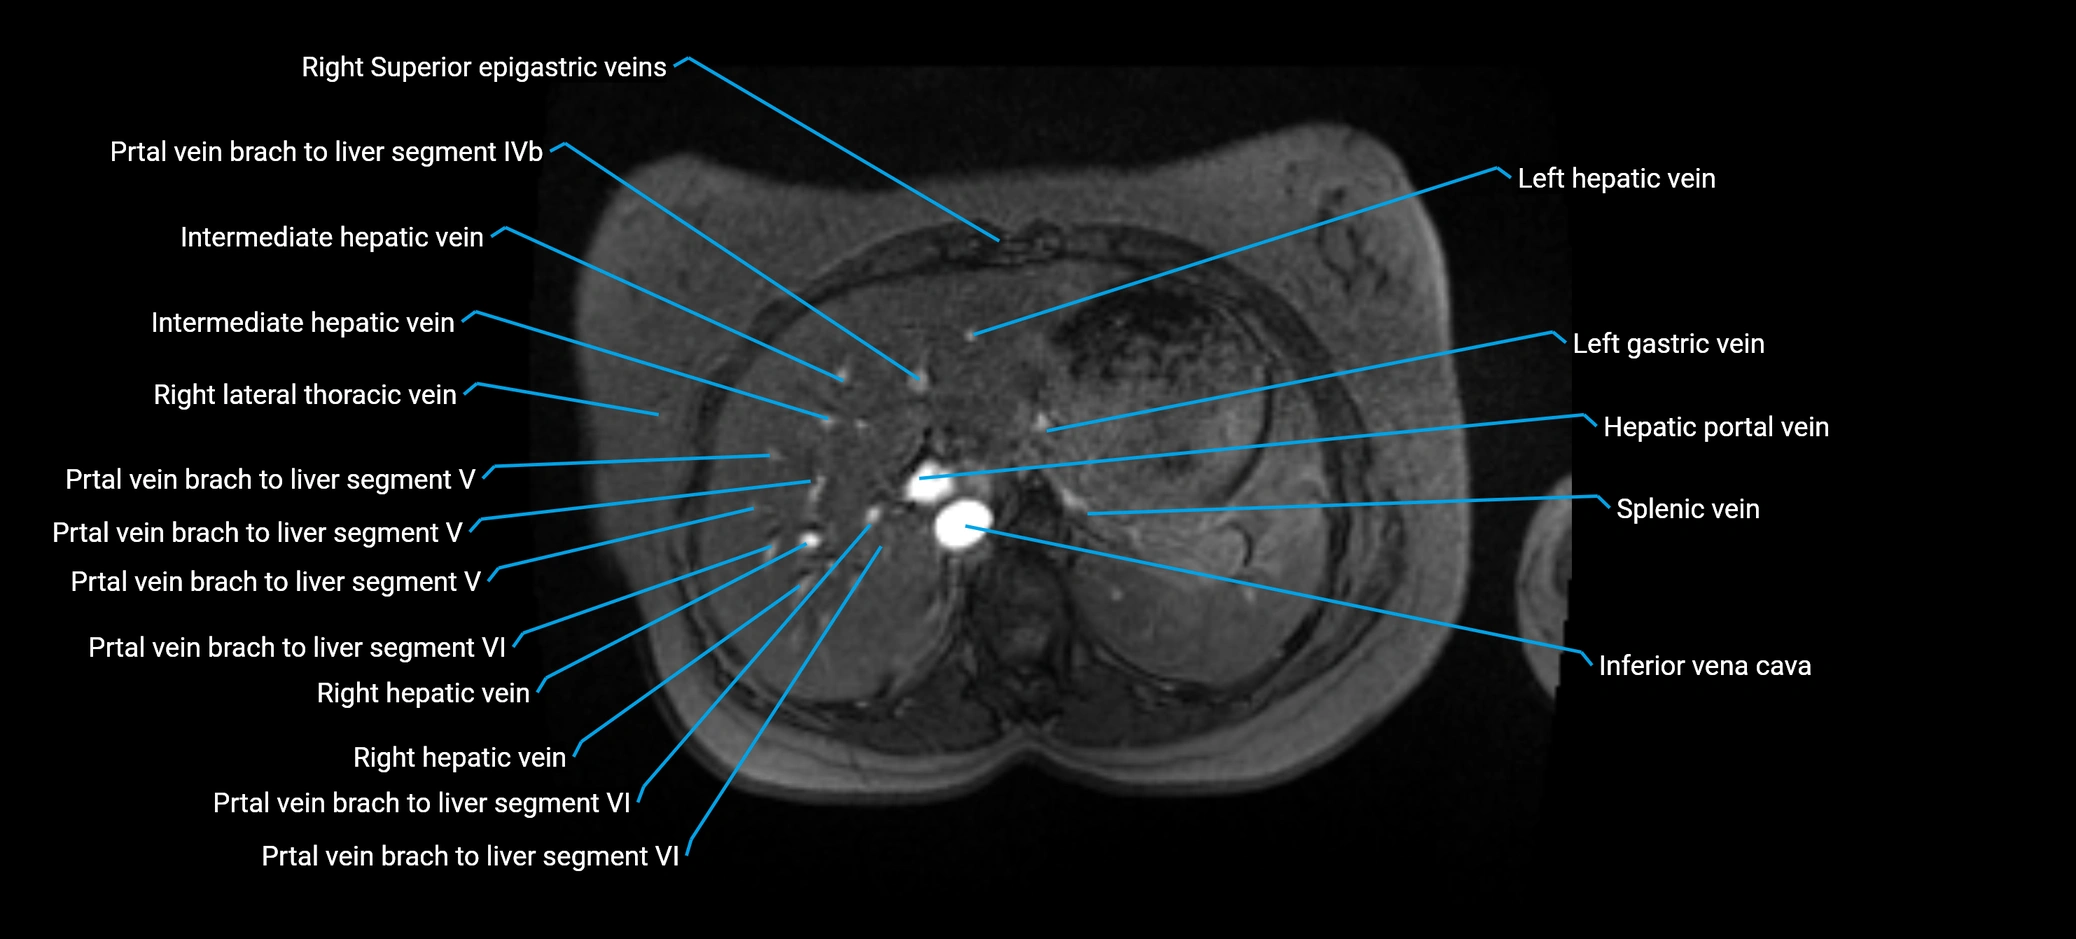

The anterior right branch of the portal vein is a major intrahepatic division of the right portal vein. After the main portal vein bifurcates into right and left branches, the right portal vein divides into anterior and posterior segmental branches.

The anterior right branch supplies the anterolateral liver segments (Segment V) and anteromedial liver segments (Segment VIII) within the right hepatic lobe. It operates as a key vascular route delivering nutrient-rich portal venous blood to the central and superior right liver.

MRV TOF (Time-of-Flight MR Venography):

• Appears as a bright, high-signal vascular channel representing flowing blood

• Clearly shows branching pattern of right portal vein into anterior and posterior branches

• Best in coronal or axial reconstructions for segmental mapping

• No need for contrast, relies on flow-related enhancement

Post-Contrast T1 Fat-Sat GRE:

• Enhances brightly and homogeneously during the portal venous phase

• Clearly delineates branching into segments V and VIII

• Best sequence for evaluating patency, caliber, and anatomic variants

MRI image

image